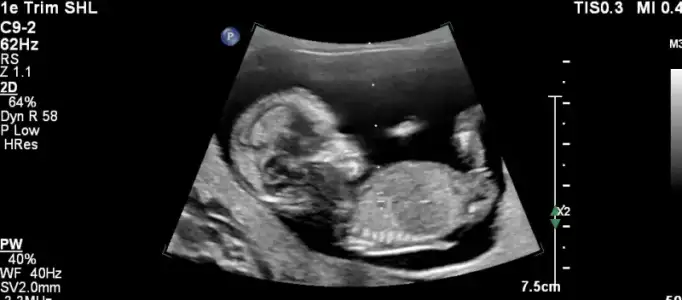

nub teorisi var canim resim at bakalim nasil

• 2.webp

2.webp

14,5 KB · Görüntüleme: 96